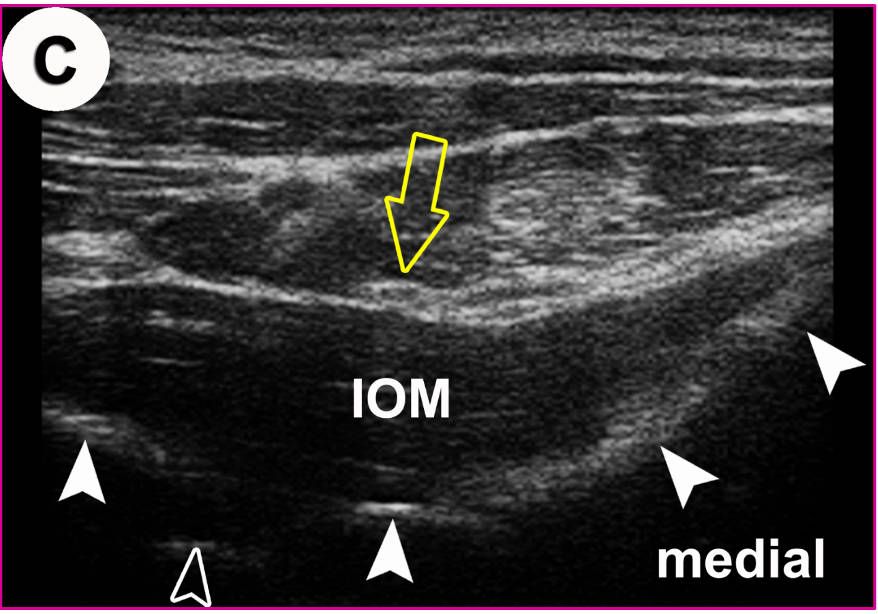

US-Darstellung und experimentelle Blockade (Pfeilköpfe: Nadel) des N. cutaneus femoris lateralis an einer Körperspenderin. Mittlerweile gängige Anwendung in der Regionalanästhesie und Schmerztherapie

Der hell erscheinende N. cutaneus femoris lateralis (Pfeil) wird am Oberschenkel in seinem „fettgefüllten Flachtunnel“ (im US dunkel!) am leichtesten aufgefunden: “POV“ (Point of Optimal Visibility) nach Prof. Moriggl.

In der US-Darstellung ist der dorsalste Anteil des ISG einsehbar (offener Pfeilkopf). Der Spalt entspricht dem radiologischen Gelenkspalt! Die knöchernen Landmarken (gefüllte Pfeilköpfe) sind aber in allen Details deutlich zu erkennen (von medial nach lateral): Crista sacralis mediana, II, Crista sacralis lateralis, Facies glutea ossis ilii.